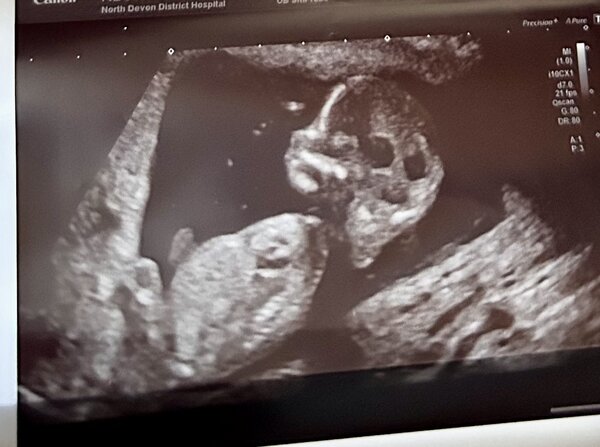

Selamlar bitanem, hayır ortadan kaybolmadım da gülüm, bu resimden net bir şey diyemiyorum soldlaki yukarı doğru çıkıntı eğer resim hatası değil ise erkek gibi görüyorum. Başka resimler var ise ekleyin değerlendireyim. Yok diyorsanız bir dahaki doktor gidişinizde lütfen yakın bir resim isteyin. Nuba göre değerlendirecekler deyin. Sevgiler hayatım 🙂